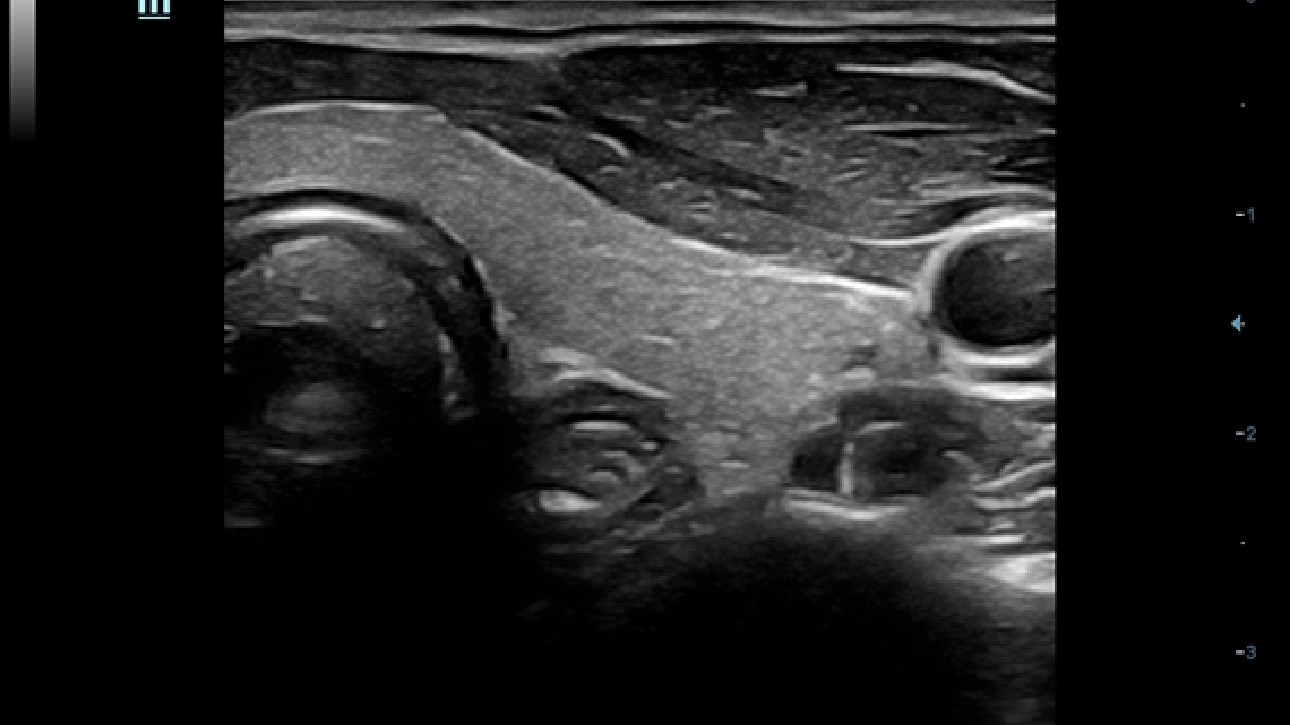

Obrazy kliniczne